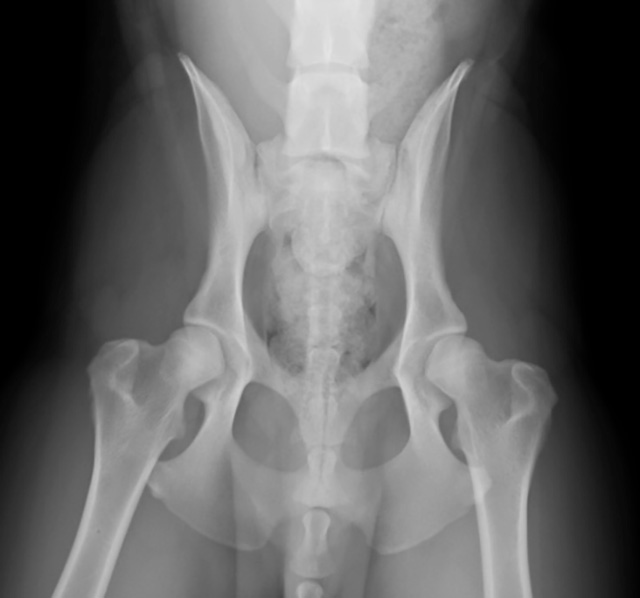

膝の靭帯が切れてしまい、足を地面につけなくなる病気です。当院では、二次診療施設での経験を活かした的確な触診とレントゲン検査で診断を行います。症状に応じた内科治療のほか、外科手術が必要な場合は、より安全で確実な実施のために高度医療施設(二次診療施設)へのスムーズなご紹介を行っています。

「歩き方が変」という症状の裏には、筋肉、骨、関節、あるいは脳・神経など、複数の原因が隠れています。当院では二次診療施設での研修経験を活かし、どこに痛みや違和感があるのかを丁寧な触診(ハンズオン検査)で見極めます。

高性能レントゲン、エコー、関節液検査などを行い、痛みの正体を突き止めます。